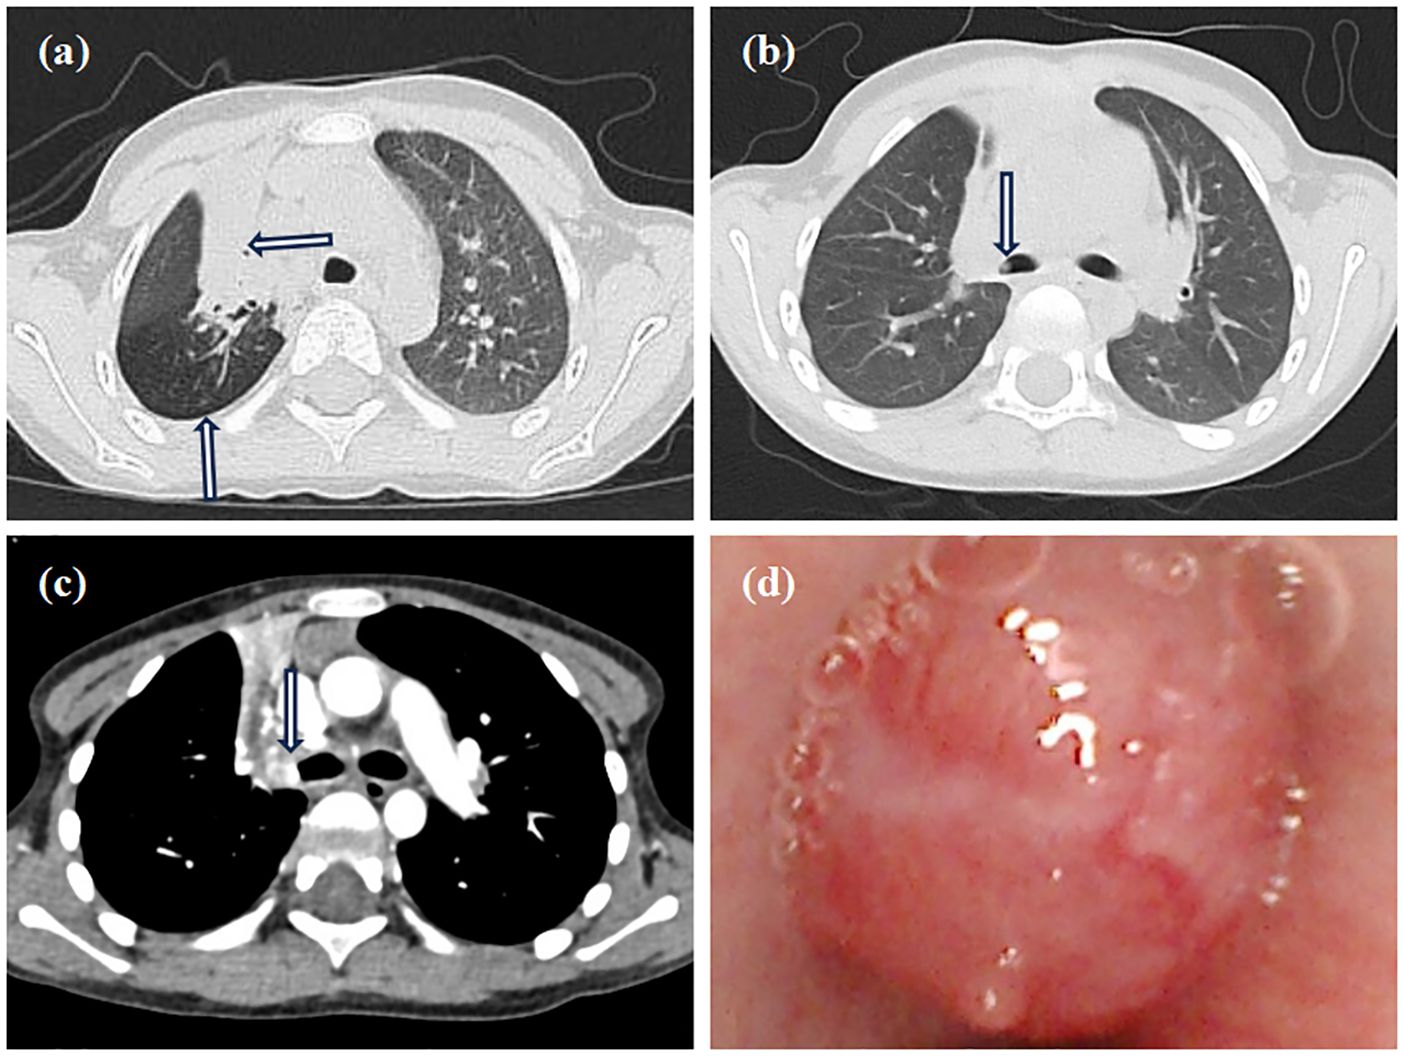

Contrast-enhanced MRI of the neck, oral cavity, and maxillofacial region revealed no abnormalities. In contrast, chest-enhanced CT imaging showed solid lesions and atelectasis in the right upper lung lobe, accompanied by localized areas of increased lucency and poor bronchial visualization (Figure 2a). Striated soft tissue density shadows were observed in the right main bronchus (Figure 2b), and a bronchial cut-off sign in the right main bronchus, accompanied by heterogeneous enhancement of the adjacent tissues (Figure 2c). Electron bronchoscopy revealed a tumor located at the orifice of the right upper lobe, causing complete airway obstruction. A prominent vascular network was visible on the tumor surface (Figure 2d). The child underwent thoracoscopic bronchial sleeve resection and right upper lobectomy under general anesthesia. The resected tumor measured 0.5 × 0.4 × 0.4 cm and extended into the bronchial lumen, encapsulated by an intact fibrous capsule. Postoperative pathological examination of lung tissue was conducted. Histologically, the tumor exhibited a solid architecture with fibrous septation and featured vesicular, microcystic, and hyaline pseudocystic structures (Figure 3a). The tumor cells were round, oval, or mildly polygonal with prominent nucleoli. The cytoplasm was eosinophilic, granular, or vacuolated, and mitotic figures were present. Occasional mucin-secreting cells were also identified (Figure 3b). No residual tumor was observed at the bronchial resection margins, and all ten examined lymph nodes were free of metastasis. Immunohistochemical analysis revealed the tumor was positive for CK7 (Figure 3c), CK8/18 (Figure 3d), AACT (Figure 3e), and partially positive for MUC1 and MUC6. It was negative for NR4A3, DOG1, Sox10, Synaptophysin, Chromogranin A, S-100, HMB45, P63, TFE3, TTF1, CK5/6, CD56, CD34, D2-40, PAX8, and CD10. CEA was positive, and the Ki-67 proliferation index was approximately 12%. Alcian blue/Periodic acid–Schiff (AB/PAS) staining highlighted, blue-stained mucus and red hyaline material within the tumor cells (Figure 3f). Following consultations by multiple expert pathologists, the final pathological diagnosis was acinic cell carcinoma. No tumor involvement was identified at the bronchial surgical margins or in the lymph nodes. At the 18-month postoperative follow-up, there was no evidence of recurrence or metastasis.

Figure 2. Imaging and bronchoscopy. (a) Chest CT shows consolidation in the right upper lobe with air trapping; (b) Chest CT shows a striated shadow in the right main bronchus; (c) The enhanced CT scan shows a bronchial cut-off sign in the right main bronchus, accompanied by heterogeneous enhancement of the adjacent tissues; (d) Electron bronchoscopy shows a neoplastic lesion in the right upper lobe, causing total airway obstruction with visible surface vessels.

Although clinical symptoms are often nonspecific, chest imaging can reveal indirect indicators of bronchial obstruction, such as atelectasis, air trapping, and bronchial dilation (8). In the present case, CT imaging demonstrated areas of solid consolidation and atelectasis in the right upper lobe, accompanied by air trapping. Bronchoscopy plays a crucial role in identifying congenital anomalies, airway compression, foreign bodies, and intraluminal masses, while also allowing for tissue biopsy to achieve a definitive pathological diagnosis (9).